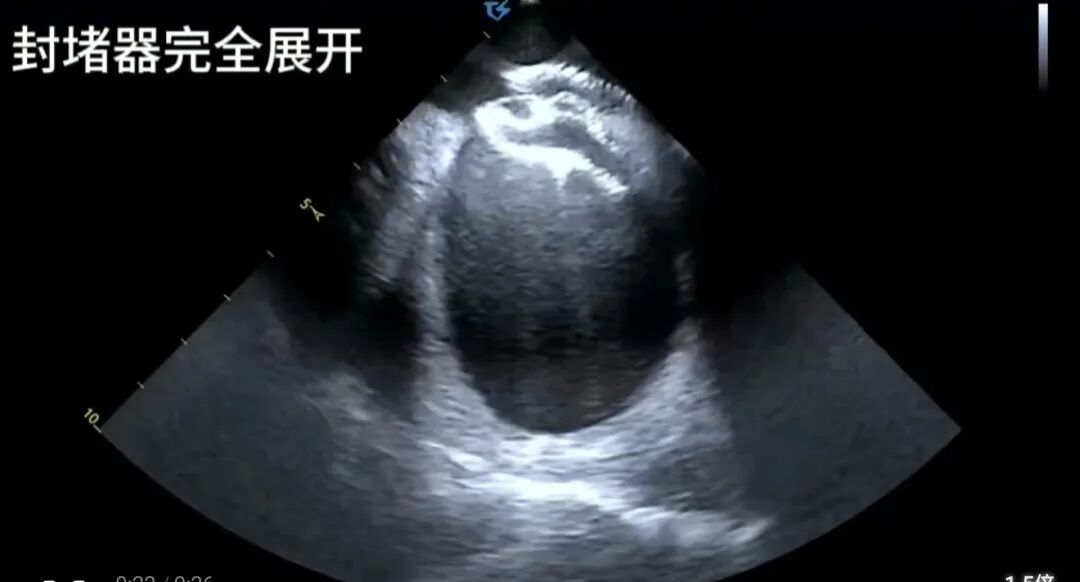

最终,一枚合适的封堵器被完美释放,术后超声提示封堵器位置固定良好,无残余分流,不影响心脏内正常血流,手术取得圆满成功。

经过周密的术前准备,电生理团队王睿、郭敏主任医师如期进行手术,术前先进行右心导管检查,结果令人振奋:患者术中实测肺动脉压仅为28mmHg,且肺血管阻力并未显著增高,这意味着其肺动脉高压在很大程度上是可逆的,并非手术的绝对“拦路虎”。这一精准判断,彻底推翻了此前“无法手术”的结论,为微创介入治疗奠定了坚实基础。本次手术全程在心腔内超声(ICE) 的实时精确引导下进行,与传统的X射线透视引导的不同之处在以下几个方面:

视野更清晰:心腔内超声探头经血管送入心脏内部,如同将“摄像头”置于心腔内,为术者提供了360度无死角的清晰视野,缺损的大小、形态、边缘以及与周边重要结构(如肺静脉、冠状静脉窦、房室瓣)的关系一目了然。

操作更精准:在超声的直视下,导丝穿越缺损、输送鞘管建立轨道、封堵器精准释放在房间隔缺损处,每一步都精准无误。

评估更即时:释放封堵器后,立即通过超声评估其位置是否稳固、是否影响周围瓣膜功能、残余分流情况,确保了手术的即时成功率与安全性。